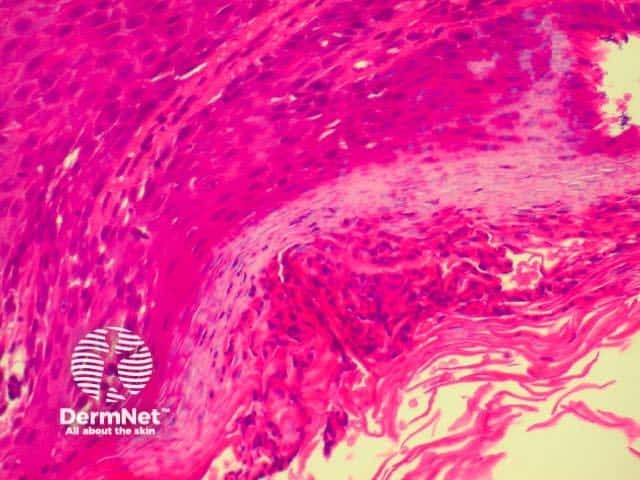

Lichen planus is the idiopathic version of a group of lichenoid disorders characterised by scaling papules or plaques. Link to a clinical description of lichen planus.

The histological features of lichen planus are:

The majority of lymphocytes in the often dense infiltrate are memory cells, identified using histochemistry by positive CD8 and CD45 RO markers.

Direct immunofluorescence nearly always reveals fibrinogen within the colloid bodies. Occasionally IgM and complement are also detected. The immunofluorescence pattern is not diagnostic as the same reactants can also be seen in systemic lupus erythematosus and erythema multiforme.

Lichen planus Lichen planus Lichen planus Lichen planus Lichen planus Lichenoid inflammation